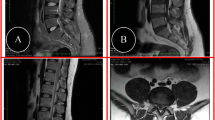

Back pain is a worldwide health problem, adding a tremendous burden to modern societies. However, little information on back health is available in China, even though a quarter of the world’s population is Chinese. To enhance knowledge in this area, we designed and initiated the Hangzhou Lumbar Spine Study, which is a cross-sectional study of a general sample of mainland Chinese with focusing on disc degeneration, Modic changes, endplate lesions, and back pain. The study consists of a structured questionnaire to measure back pain history and lifetime exposure to suspected risk factors, magnetic resonance imaging of the lumbar spine, bone mineral density study of the spine and hip, and DNA sample analysis. Here we briefly introduce the study methodology, report the test-retest reliability of the questionnaire, and describe the cohort profile to date. Since May 2014, 301 randomly selected subjects (male/female, 122/179; mean age, 51.0 years; range, 20–87 years) have been recruited. Tests-retests of the questionnaire, completed by 40 participants, revealed good reliability. To our knowledge, the Hangzhou Lumbar Spine Study is the first population-based epidemiological study conducted to characterize lumbar spinal phenotypes and back pain, their interaction, and their associations with lifetime environmental exposure, in mainland Chinese. Epidemiological information obtained from a reliable questionnaire, magnetic resonance (MR) imaging data, dual energy X-ray absorptiometry (DXA) measurements, and DNA analysis may serve as a valuable reference for future studies on back health, particularly for mainland Chinese.

开展了中国大陆第一个基于大样本的有关腰痛、 腰椎间盘退变、终板病损、Modic 改变的流行病 学研究;开发了一份可信度高的包含腰痛病史以 及相关风险因素的调查问卷;采用高分辨率3.0 T 核磁共振来分辨腰椎病变特征。

从杭州采荷社区中随机抽取人群,完成调查问卷 腰痛相关信息记录、腰椎核磁共振扫描、腰椎及 股骨颈骨密度测量以及血液样本抽取。从参与人 群重复抽取40 人进行问卷可信度测量。调查问 卷包含的信息包括,人群一般资料、吸烟史、腰 痛史、职业史以及运动史,用来记录腰痛发生情 况以及相关风险因素。腰椎核磁共振扫描用于观 察椎间盘退变、Modic 改变以及终板病损等腰椎 特征性病变。骨密度测量用来研究与腰椎特征性 病变的联系。血液样本用于后续遗传因素的分 析。